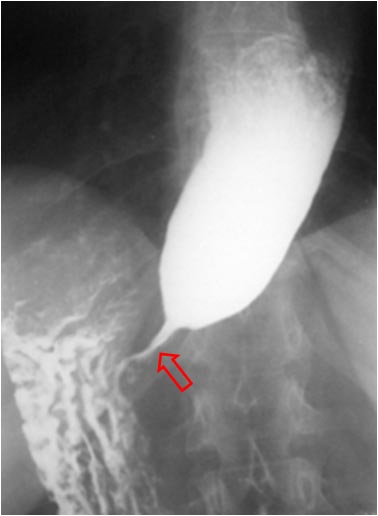

SIGNO DEL PICO

Signo de vólvulo y otras causas de obstrucción intestinal en asa cerrada, que inicialmente se describió en el estudio baritado (enema opaco). Se refiere a la estenosis fusiforme que se dirige al punto de torsión (flecha roja en la radiografía y flecha negra en el esquema). En caso de que el contraste atraviese la estenosis y exista una disminución de la luz en el segmento proximal de la torsión, la imagen obtenida recuerda a la de dos pájaros con sus picos juntos.

La imagen muestran el Signo del pico en un paciente con un vólvulo de sigma.

Aunque lo hemos incluido dentro de los signos de colon, este signo también es visible en las obstrucciones en asa cerrada de intestino delgado.

Inicialmente descrito en el enema opaco, en la TC también es visible este signo y no solamente en el asa eferente (como ocurre en el enema opaco, donde este asa se rellena retrógradamente) sino también en el aferente.

Existe otro Signo del pico en la achalasia, afectando al esófago distal, ya descrito en la sección correspondiente (ABDOMEN/Tubo digestivo/Esófago).